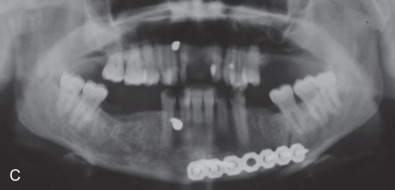

All of these systems allowed for convalescent function – life without MMF. RIF had the potential of dramatically shortening the course of treatment. However, its use was highly technique-sensitive with a steep learning curve. Thus, the incidence of complications increased dramatically due to operator error. Complications related to inadequate reduction – “the OIF” (open internal fixation … without the reduction) ( Figs. 1.16.1–1.16.3 ), inadequate fixation ( Figs. 1.16.4–1.16.7 ) and surgical misadventure ( Fig. 1.16.8 ) began to appear. Indeed, by the early 1990s operator error was the number one cause of mandibular fracture complications. Quite obviously, RIF is very unforgiving. When done poorly, one has a rigidly fixed mistake. The latest series of misadventures are related to the use of IMF screws. Bone-anchored arch bars will most likely be next. Not all believe that RIF and convalescent function is cost-effective with respect to the increased cost, potential for complications, and patient acceptance.